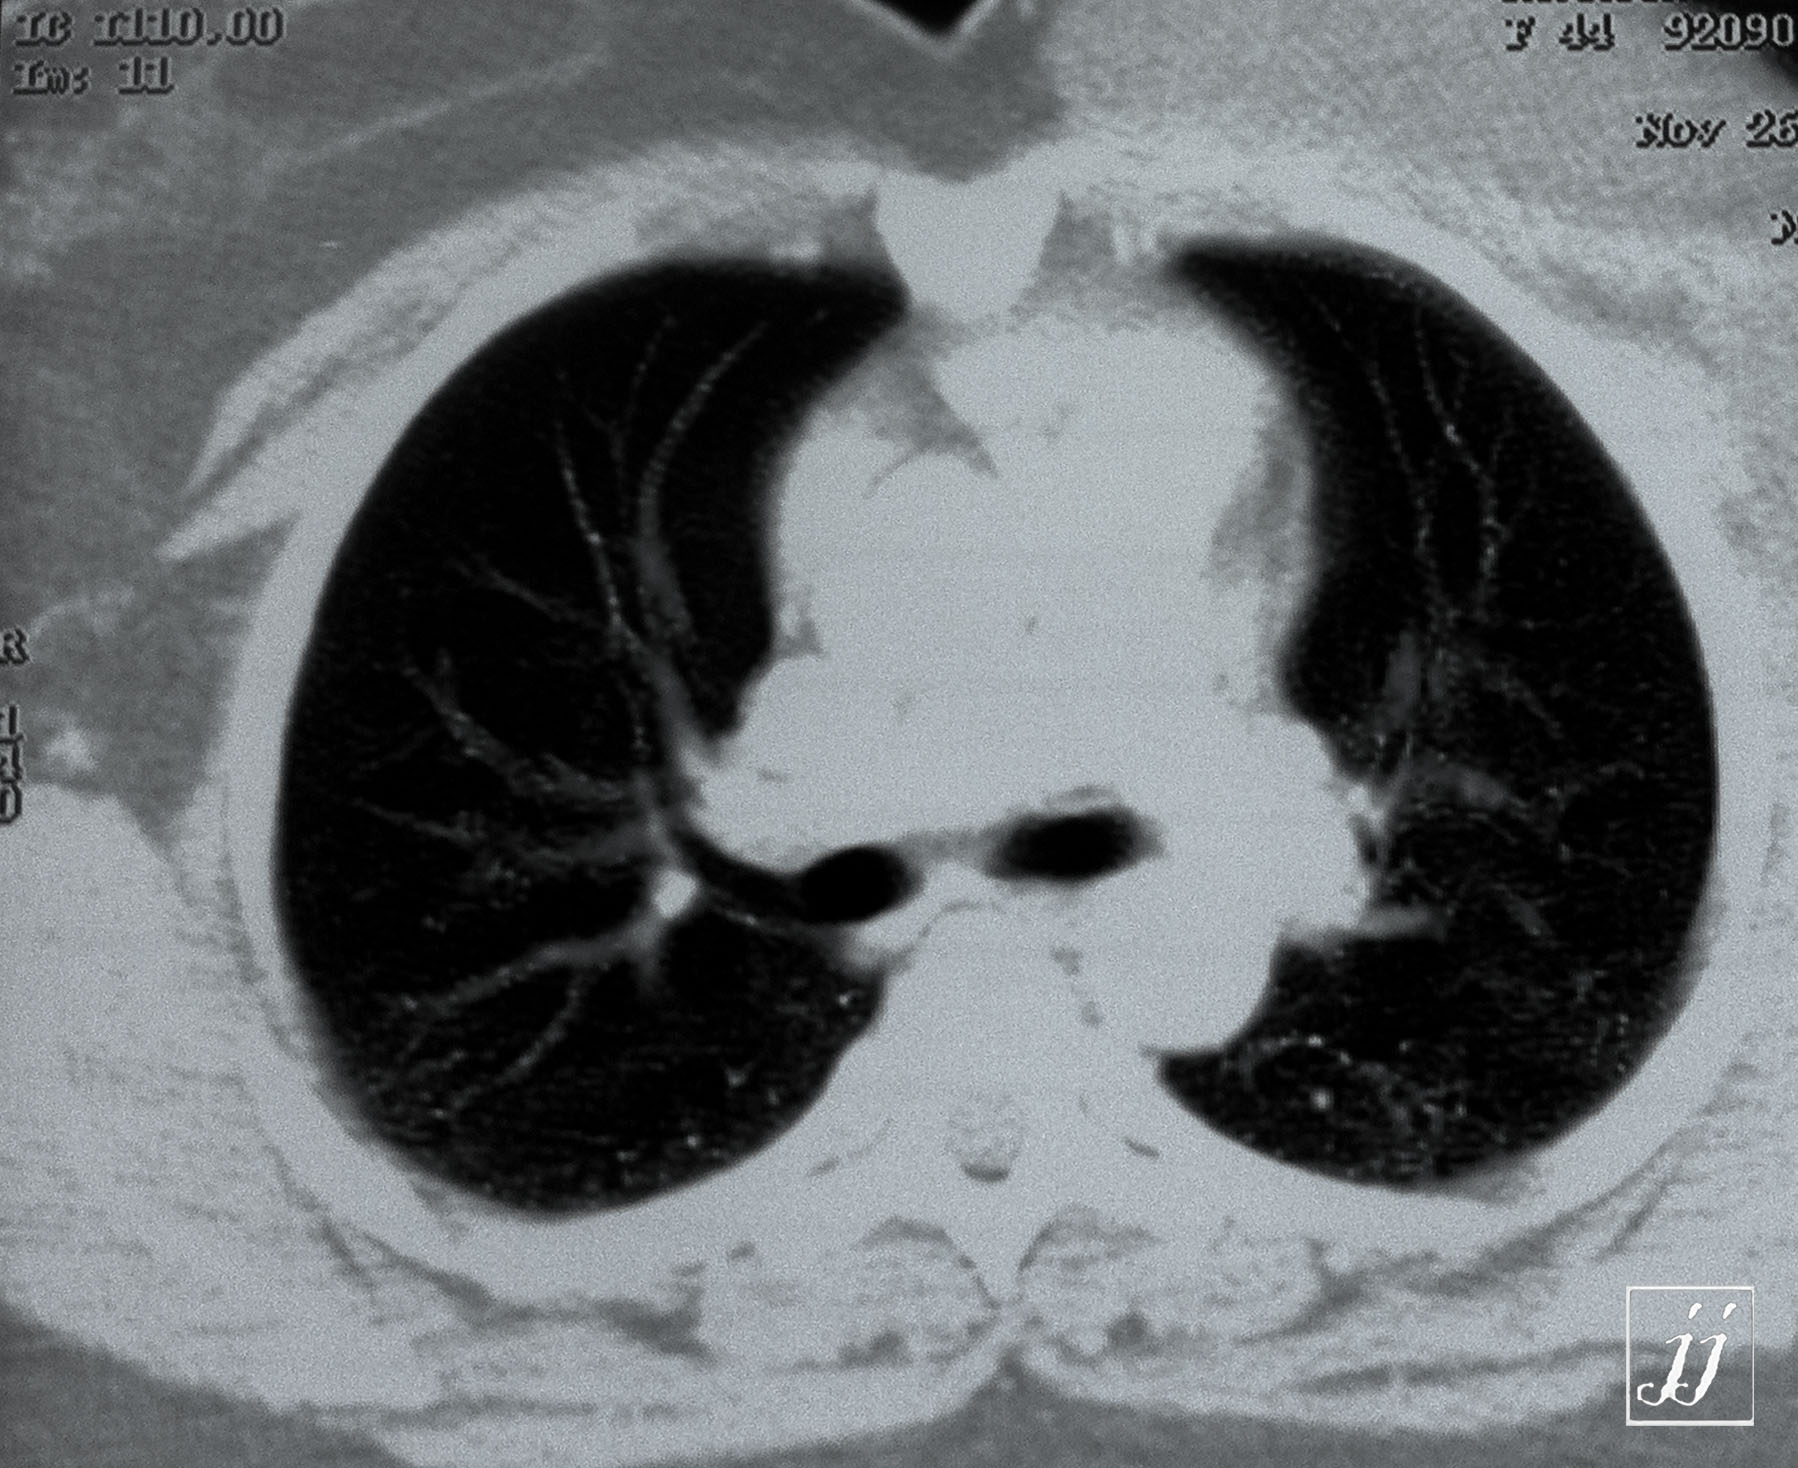

Breast- left breast silicon (1)